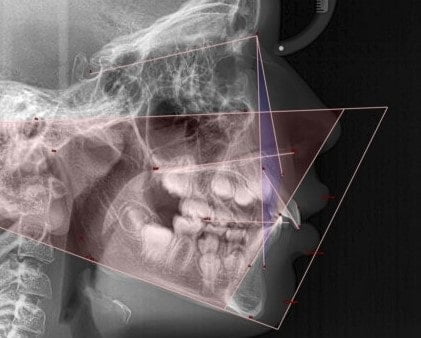

Les radiographies dentaires seront également analysées avec précision.